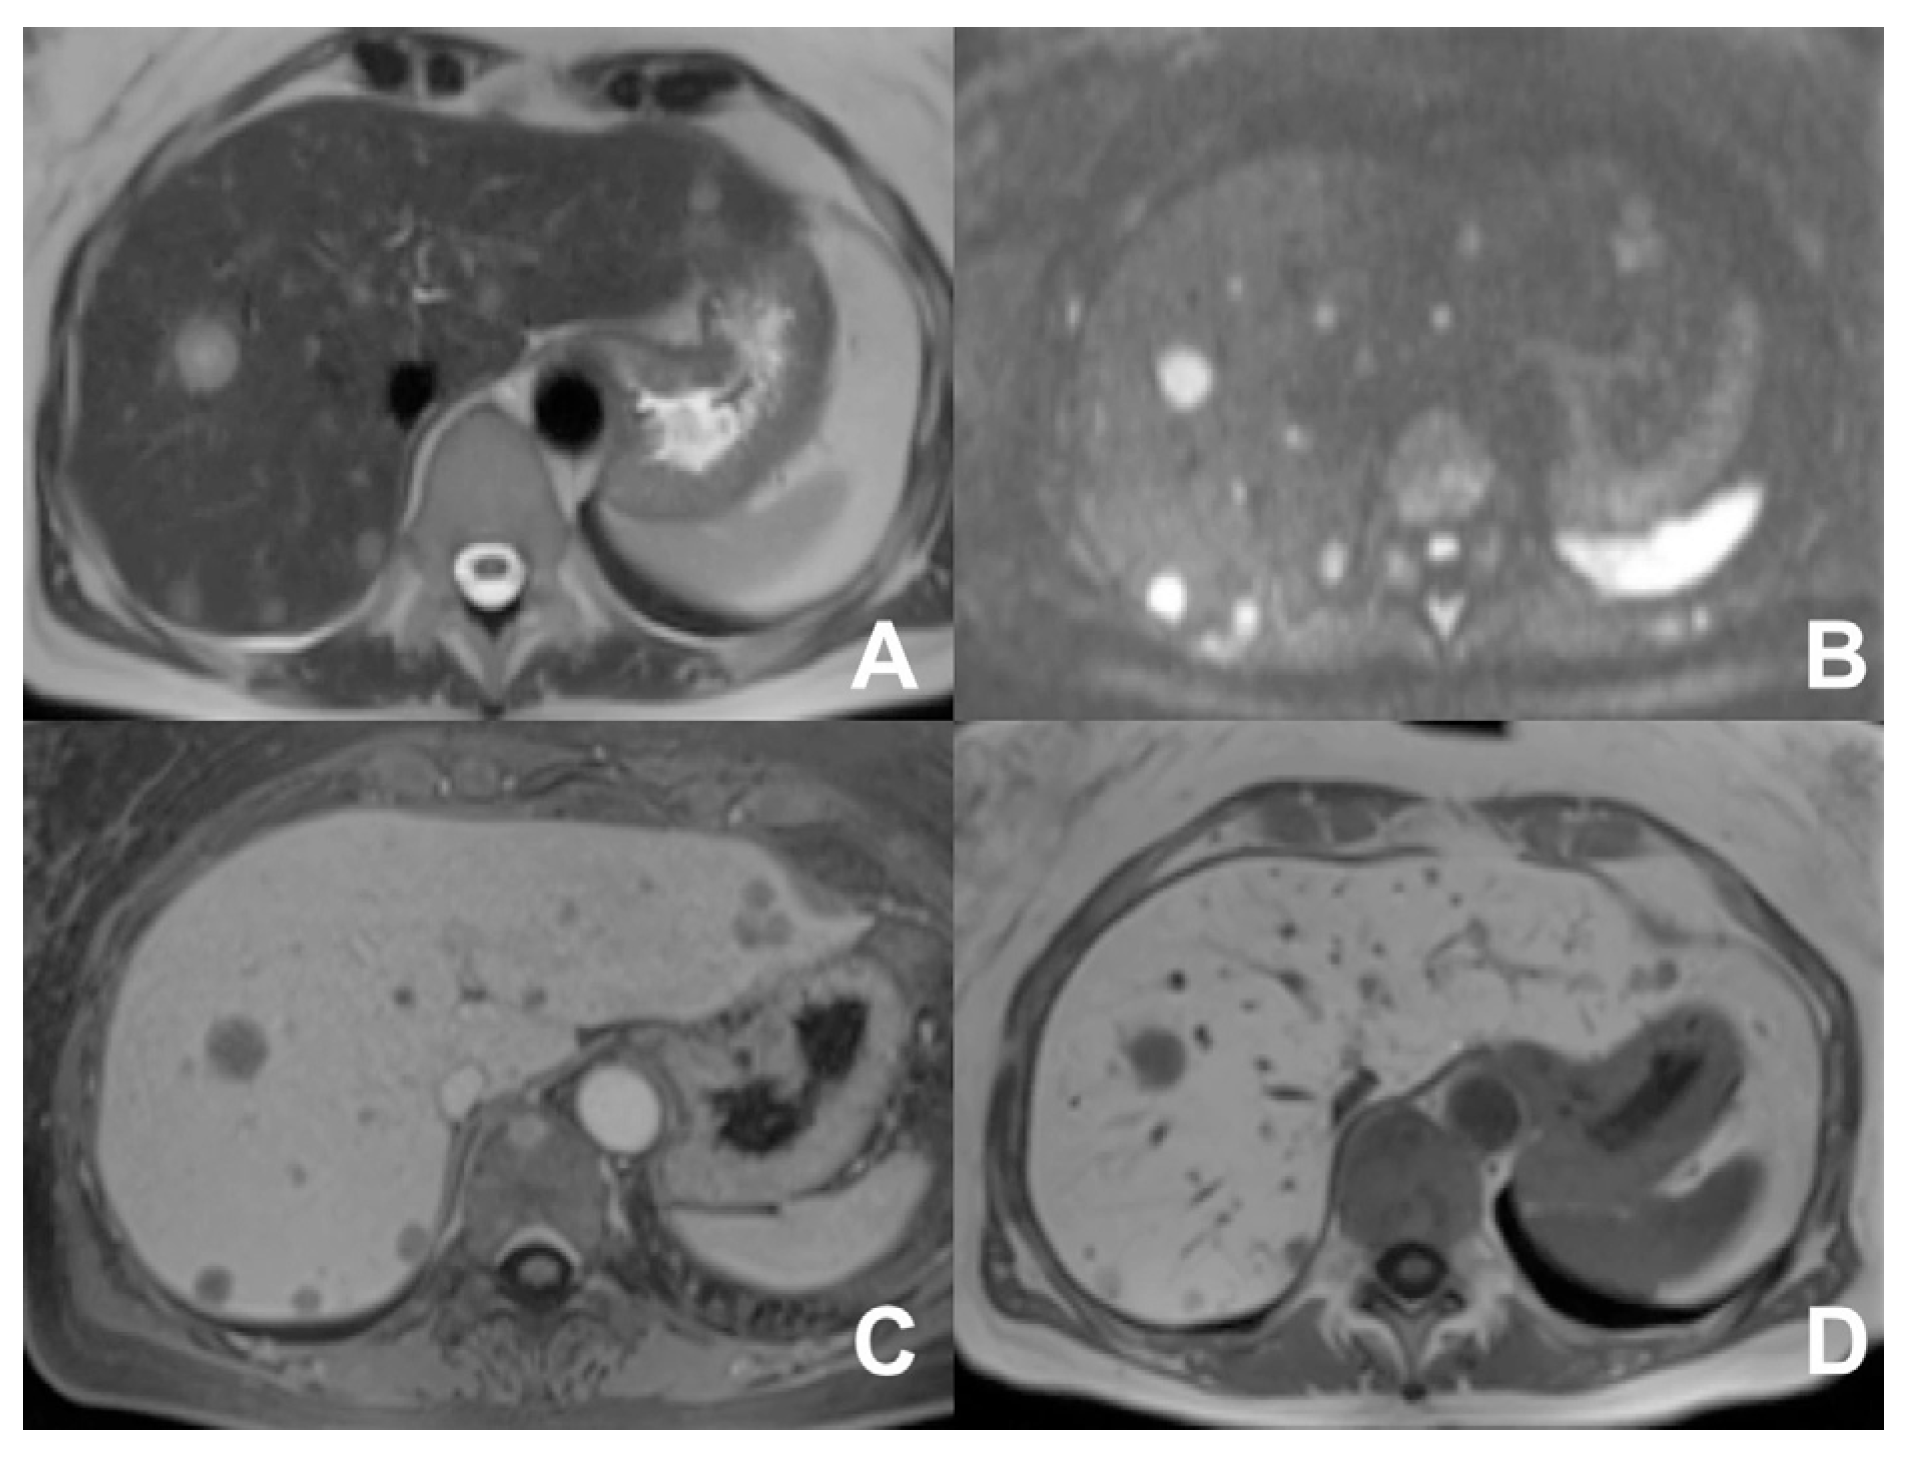

| DWI b 0–50–400–800 | AXIAL | -- | -- | DWI b50 increases the sensitivity of mets detection | |

| GRE T1 IN/OUT | AXIAL | -- | -- | Steatosis | |

| GRE T1 3D DYNAMIC | AXIAL | PRE-ART 25″-PORTAL 70″-LATE 180″ | YES | HBP increases the sensitivity of metastases detection | |

- Floriani, I.; Torri, V.; Rulli, E.; Garavaglia, D.; Compagnoni, A.; Salvolini, L.; Giovagnoni, A. Performance of imaging modalities in diagnosis of liver metastases from colorectal cancer: A systematic review and meta-analysis. J. Magn. Reson. Imaging 2010, 31, 19–31. [Google Scholar] [CrossRef] [PubMed]

- Sobeh, T.; Inbar, Y.; Apter, S.; Soffer, S.; Anteby, R.; Kraus, M.; Konen, E.; Klang, E. Diffusion-weighted MRI for predicting and assessing treatment response of liver metastases from CRC—A systematic review and meta-analysis. Eur. J. Radiol. 2023, 163, 110810. [Google Scholar] [CrossRef] [PubMed]